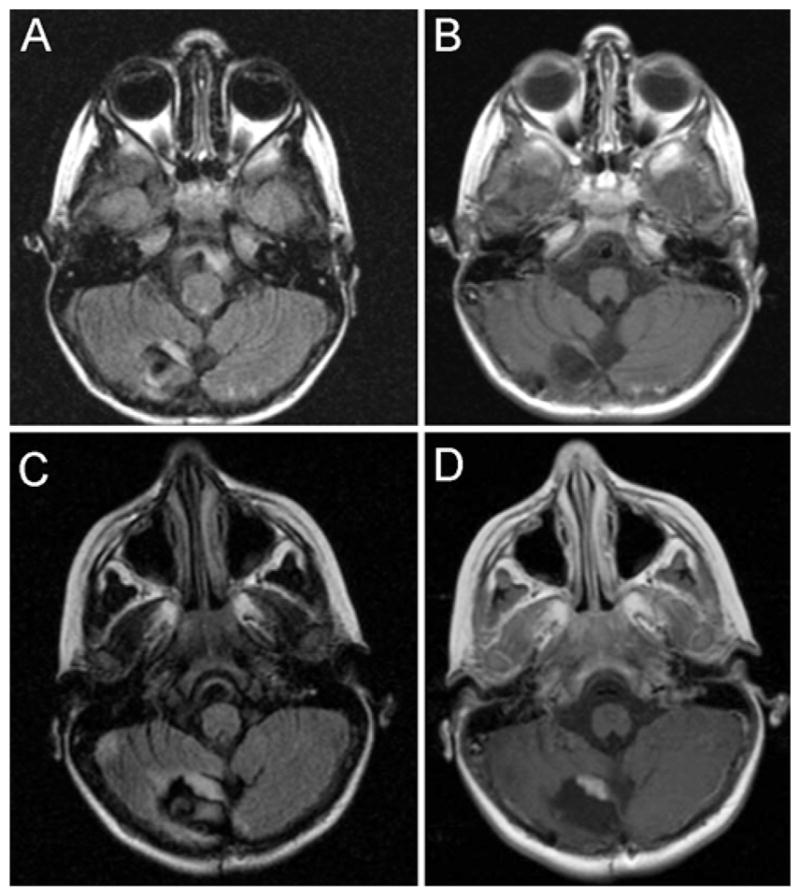

We investigated the available images in our study patients to identify potential early radiographic markers of recurrence in patients with JPA or ganglioglioma, the largest 2 tumor subgroups in our population. Of the 67 patients in our study, 46 underwent GTR of a JPA or ganglioglioma and had immediate and early postoperative imaging (up to 12 months postoperatively), as well as later follow-up imaging, that we could examine (6 patients with recurrence and 40 with no recurrence). Among the patients in whom recurrence was observed, we found that nodular FLAIR signal in the tumor cavity on the immediate postoperative MR image that persisted to the first interval postoperative MR image might be a useful marker for recurrence. An example of this persistent nodular FLAIR signal that correlates with the future site of enhancing recurrent tumor is presented in Fig. 2. A preliminary univariate analysis of this particular radiographic finding among the subset of 46 patients (Table 3) revealed a significant correlation between persistent nodular FLAIR signal and recurrence defined by contrast enhancement at the same site (Fisher exact test, p < 0.0216). A major caveat of this analysis is that 2 of the 6 patients with recurrence showed evidence of recurrent tumor on the 3-month interval surveillance images; therefore, this persistent FLAIR signal on the 3-month MR scan was coincident with a contrast-enhancing nodule. Additionally, as seen in the group of patients without recurrence, persistent nodular FLAIR signal was a common finding (42.5%) and thus was not highly specific. However, the absence of a persistent nodular FLAIR signal in the setting of GTR for JPA or ganglioglioma may be a useful prognostic marker for a lower likelihood of recurrence.

Fig. 2.

Postoperative axial MR images of a pediatric patient following GTR of a JPA that recurred. The 5-month postoperative imaging study demonstrates persistent nodular FLAIR signal abnormality in the tumor cavity (A) in the absence of contrast enhancement (B). The 12-month postoperative MR image reveals a thickened FLAIR signal abnormality in the same location (C) with new overlapping contrast enhancement (D).

Significant remaining challenges include the development of guidelines for postoperative MRI surveillance beyond 10 years and the identification of factors that might predict future recurrence. Currently, we would recommend a 5-year surveillance schedule beyond 10 years. However, evidence-based recommendations are not possible at this time due to insufficient follow-up data beyond 10 years in the MRI era in pediatric patients with low-grade glial and glioneuronal tumors. An earlier report by Dorward and colleagues described early nodular enhancement at 3–6 months, high Ki 67 labeling index, and CD68 positivity as potential predictors of recurrence in patients with JPA following GTR.4 In our series, those patients with early nodular enhancement at 3–6 months were considered to have recurrent JPA, and 2 of these patients underwent repeat resection with pathologically proven evidence of tumor. In our preliminary analysis of radiographic features predictive of recurrence, we found that for JPAs and gangliogliomas, a persistent nodular FLAIR signal in the tumor cavity seen on both the immediate and first postoperative MR scan (within 12 months) may be predictive of recurrence. More strikingly, the absence of this radiographic finding may predict a very low likelihood of recurrence. These data also suggest that a patient’s first interval postoperative MR scan, rather than the immediate postoperative scan, should be considered the patient’s baseline postoperative study. Clearly, larger numbers of patients with adequate sequential MRI and multivariate analyses of recurrence are required to validate these preliminary findings. Future studies are needed to determine the appropriate frequency of long-term surveillance and to identify prognostic indicators that might predict recurrence among these patients.